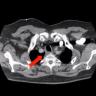

Mediastinum

This video demonstrates a robotic excision of a parathyroid adenoma in the mediastinum sitting adjacent to a patent LIMA graft from a previous CABG.